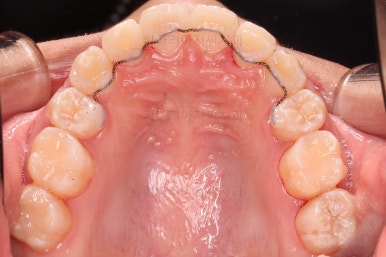

장치를 부착했어요.

윗니는 상대적으로 많이 보이기 때문에 세라믹, 아랫니는 많이 보이지 않기 때문에 메탈로 부착했어요.

동래교정치과 장치를 부착한 직후의 모습입니다.

입은 약간 더 튀어나오는 편이었고 상대적으로 많이 보이는 윗니를 세라믹으로 해서 아랫니는 메탈이라 하더라도 심미적으로 크게 손해는 아니었어요.